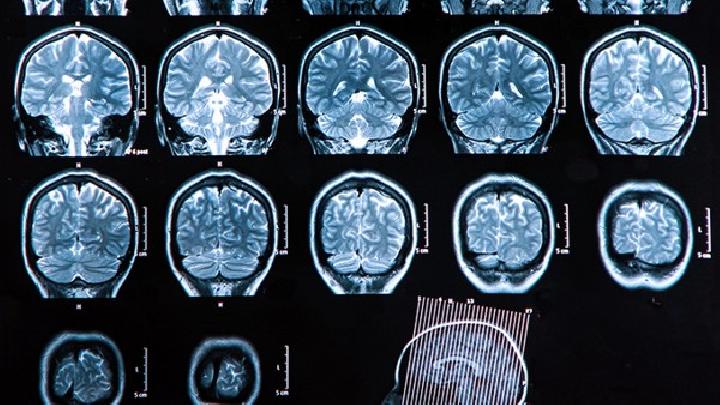

脑积水的专业治疗导航地图